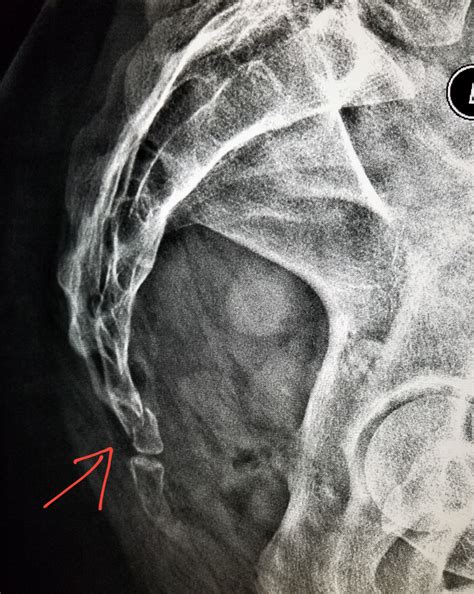

• Imaging Tests: X-rays, CT scans, or MRI scans may be ordered to visualize the tailbone and confirm the fracture.